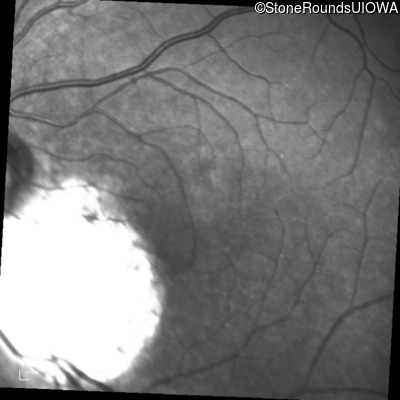

Infrared Fundus Photograph - Left - 20/50 +2

Exemplar